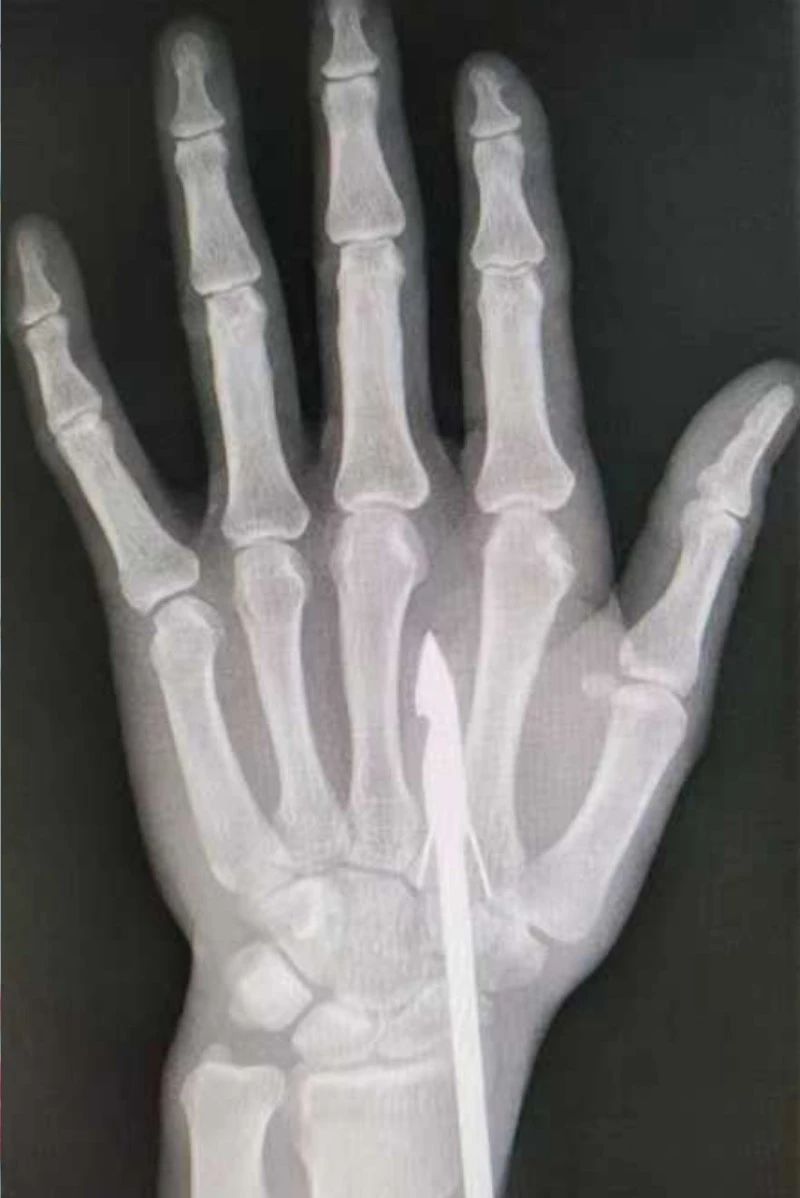

時間緊迫,每一秒的流逝都可能對傷者的手部功能造成不可逆的損害。接診醫(yī)生代彭威,迅速對傷者進行了初步檢查。他注意到,魚鉤已經(jīng)深深嵌入皮膚,情況遠比表面看起來復(fù)雜。沒有絲毫猶豫,立即安排了X線檢查以確認魚鉤的位置及傷及范圍,以及急診化驗檢查以評估患者的整體狀況。

確保在取出魚鉤的同時,不對周圍的組織造成額外的傷害。8點15分左右患者在局部浸潤麻下進行手術(shù),經(jīng)探查后魚鉤未傷及重要血管、神經(jīng)及肌腱,經(jīng)過緊張的十分鐘,魚鉤終于被順利取出,隨后對傷口進行了仔細的清理和縫合,用敷料仔細包扎,確保傷口能夠順利愈合。